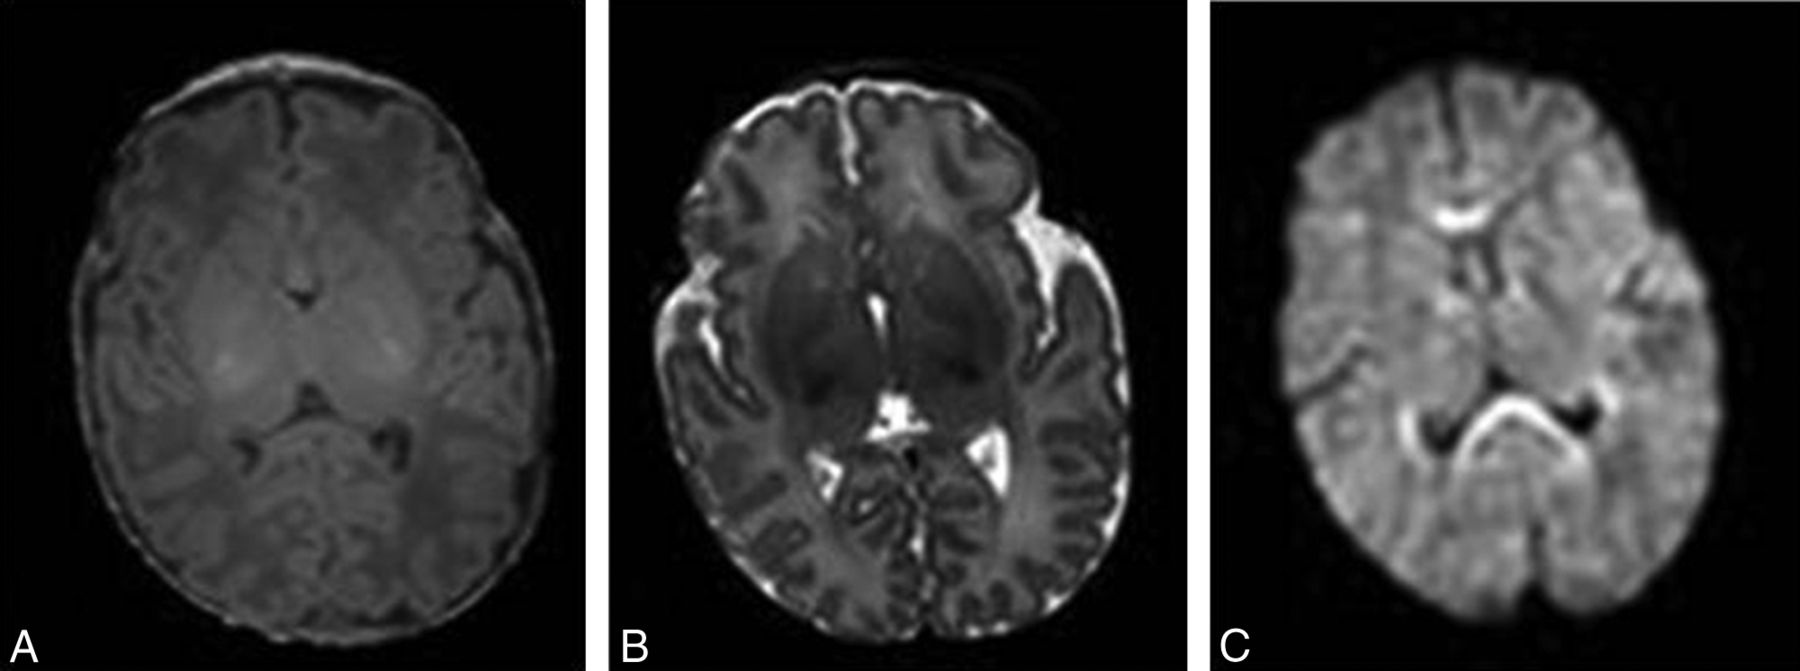

MR imaging is an ideal diagnostic technique for the evaluation of infants and fetuses1⇓⇓⇓⇓⇓–7 because of the absence of ionizing radiation, the superior contrast of soft tissues compared with sonography, and the availability of different contrast options (T1-weighted, T2-weighted, and diffusion-weighted imaging, Fig 1) to improve characterization of both anatomy and pathology. However MR imaging remains a relatively slow technique, with scanning times for most applications in the order of seconds to minutes, leaving them susceptible to motion artifacts. The normally mobile fetus and the unsettled neonate present a major difficulty because the presence of motion during a long acquisition will decrease image quality in the form of motion artifacts (Fig 2), hamper accurate image interpretation, and often necessitate a repeat MR imaging to establish a diagnosis. This may have major emotional implications for parents and can stress the tight budgets of health care providers.

T1-weighted (A), T2-weighted (B), and diffusion-weighted (C) axial MR brain images of a 5-day-old full-term neonate without motion artifacts acquired at 1.5T.